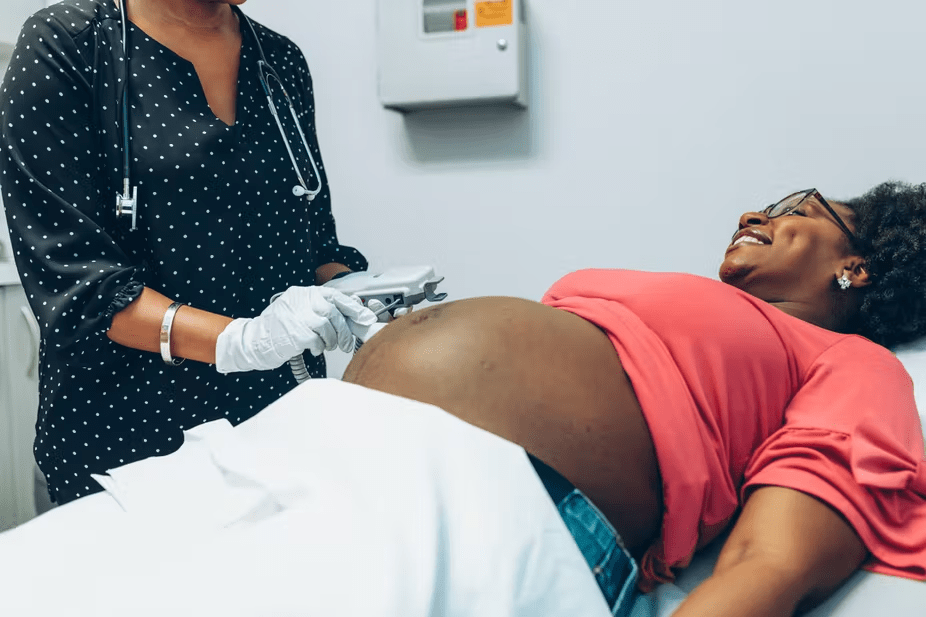

Our team of qualified healthcare professionals brings years of experience across various medical disciplines, ensuring that you receive personalized care tailored to your unique needs. From everyday consultations to specialized services such as antenatal care, family planning, wound management, and chronic disease support, we are committed to being your trusted health partner.

Sonar (Ultrasound)

Antenatal Care